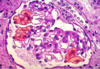

What is wrong with this glomerulus?

proliferative damage can be seen here were there is increased numbers of cells and inflammation